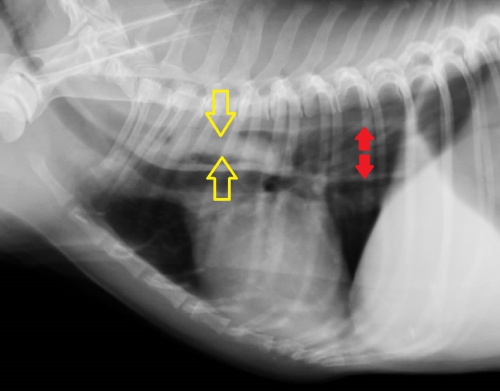

飼い主さんからの申告により、食道内異物はほぼ確実ですのでレントゲン撮影を胸部と腹部で行いました。

下の写真が胸部レントゲン写真です。黄色い矢印に挟まれた「白く細長い異物が見えると思います。この場所は胸部食道の心基底部(心臓の上)に近い部分で、食道閉塞を起こしやすい場所です。写真ではまた。食道閉塞に伴って飲み込んだ空気によって食道拡張がみられています。(右の赤い矢印の間)

ふつう、食道はレントゲン写真に写らないのですが、このわんちゃん、かなり苦しかったらしく大量の空気を飲んでおり、食道と胃に空気が入っています。このため、飲みこんだ空気が「造影剤」となって、異物が「空気造影」されており、幸いにもレントゲン写真で異物の存在が明らかになりました。

食道の状況を見るためにバリウム造影を行ったのが右下の写真です。造影剤は異物の周囲を速やかに通り抜けており、異物は食道に密着している状態ではない様子ですが、どうも両端で食道に引っかかっているような感じではないでしょうか。